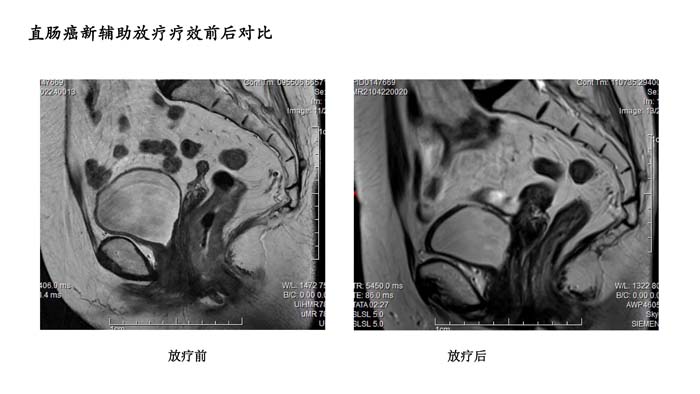

直肠癌新辅助放疗疗效前后对比3

- 直肠癌新辅助放疗疗效前后对比3